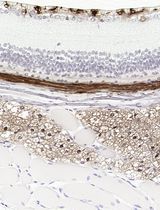

In this protocol, we describe the use of a calvarial injection model which tests the ability of agents to stimulate bone formation in vivo. This method requires only small amounts of the stimulatory agent, and was first described by Cornish (Cornish et al., 1993) to resolve the controversy of whether leukemia inhibitor factor could promote bone formation. We have adapted the Cornish method to include calcein labelling to allow measurement of bone formation, and we have made use of it to test a range of cytokines including oncostatin M (Walker et al., 2010), cardiotrophin-1 (Walker et al., 2008), and most recently IL-6 acting through its soluble receptor (McGregor et al., 2019). We have also used this method to determine whether responses to cytokines are modified in mice with a cell-specific deletion of gp130, the common receptor used by these cytokines (Johnson et al., 2014). We provide here a full description of how to carry out the in vivo protocol, and how to embed and section tissues using undecalcified histology techniques; micro-computed tomography can also be used for assessment, but this does not allow measurement of bone formation rate using calcein labels. An abbreviated form of this method using single calvarial injections or two days of calvarial injections can also be used to assess gene responses elicited by cytokines in vivo by Western blot (Walker et al., unpublished) and effects on protein expression by immunohistochemistry (Walker et al., 2010).